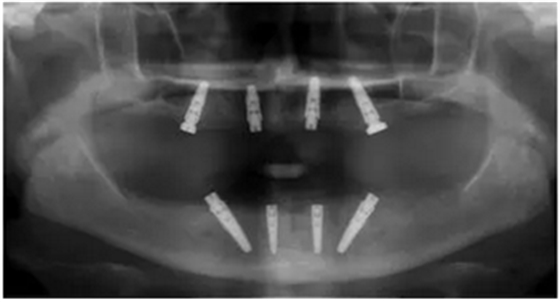

手術(shù)后90天拍攝連帶內(nèi)錐形連接愈合基臺的X光片。